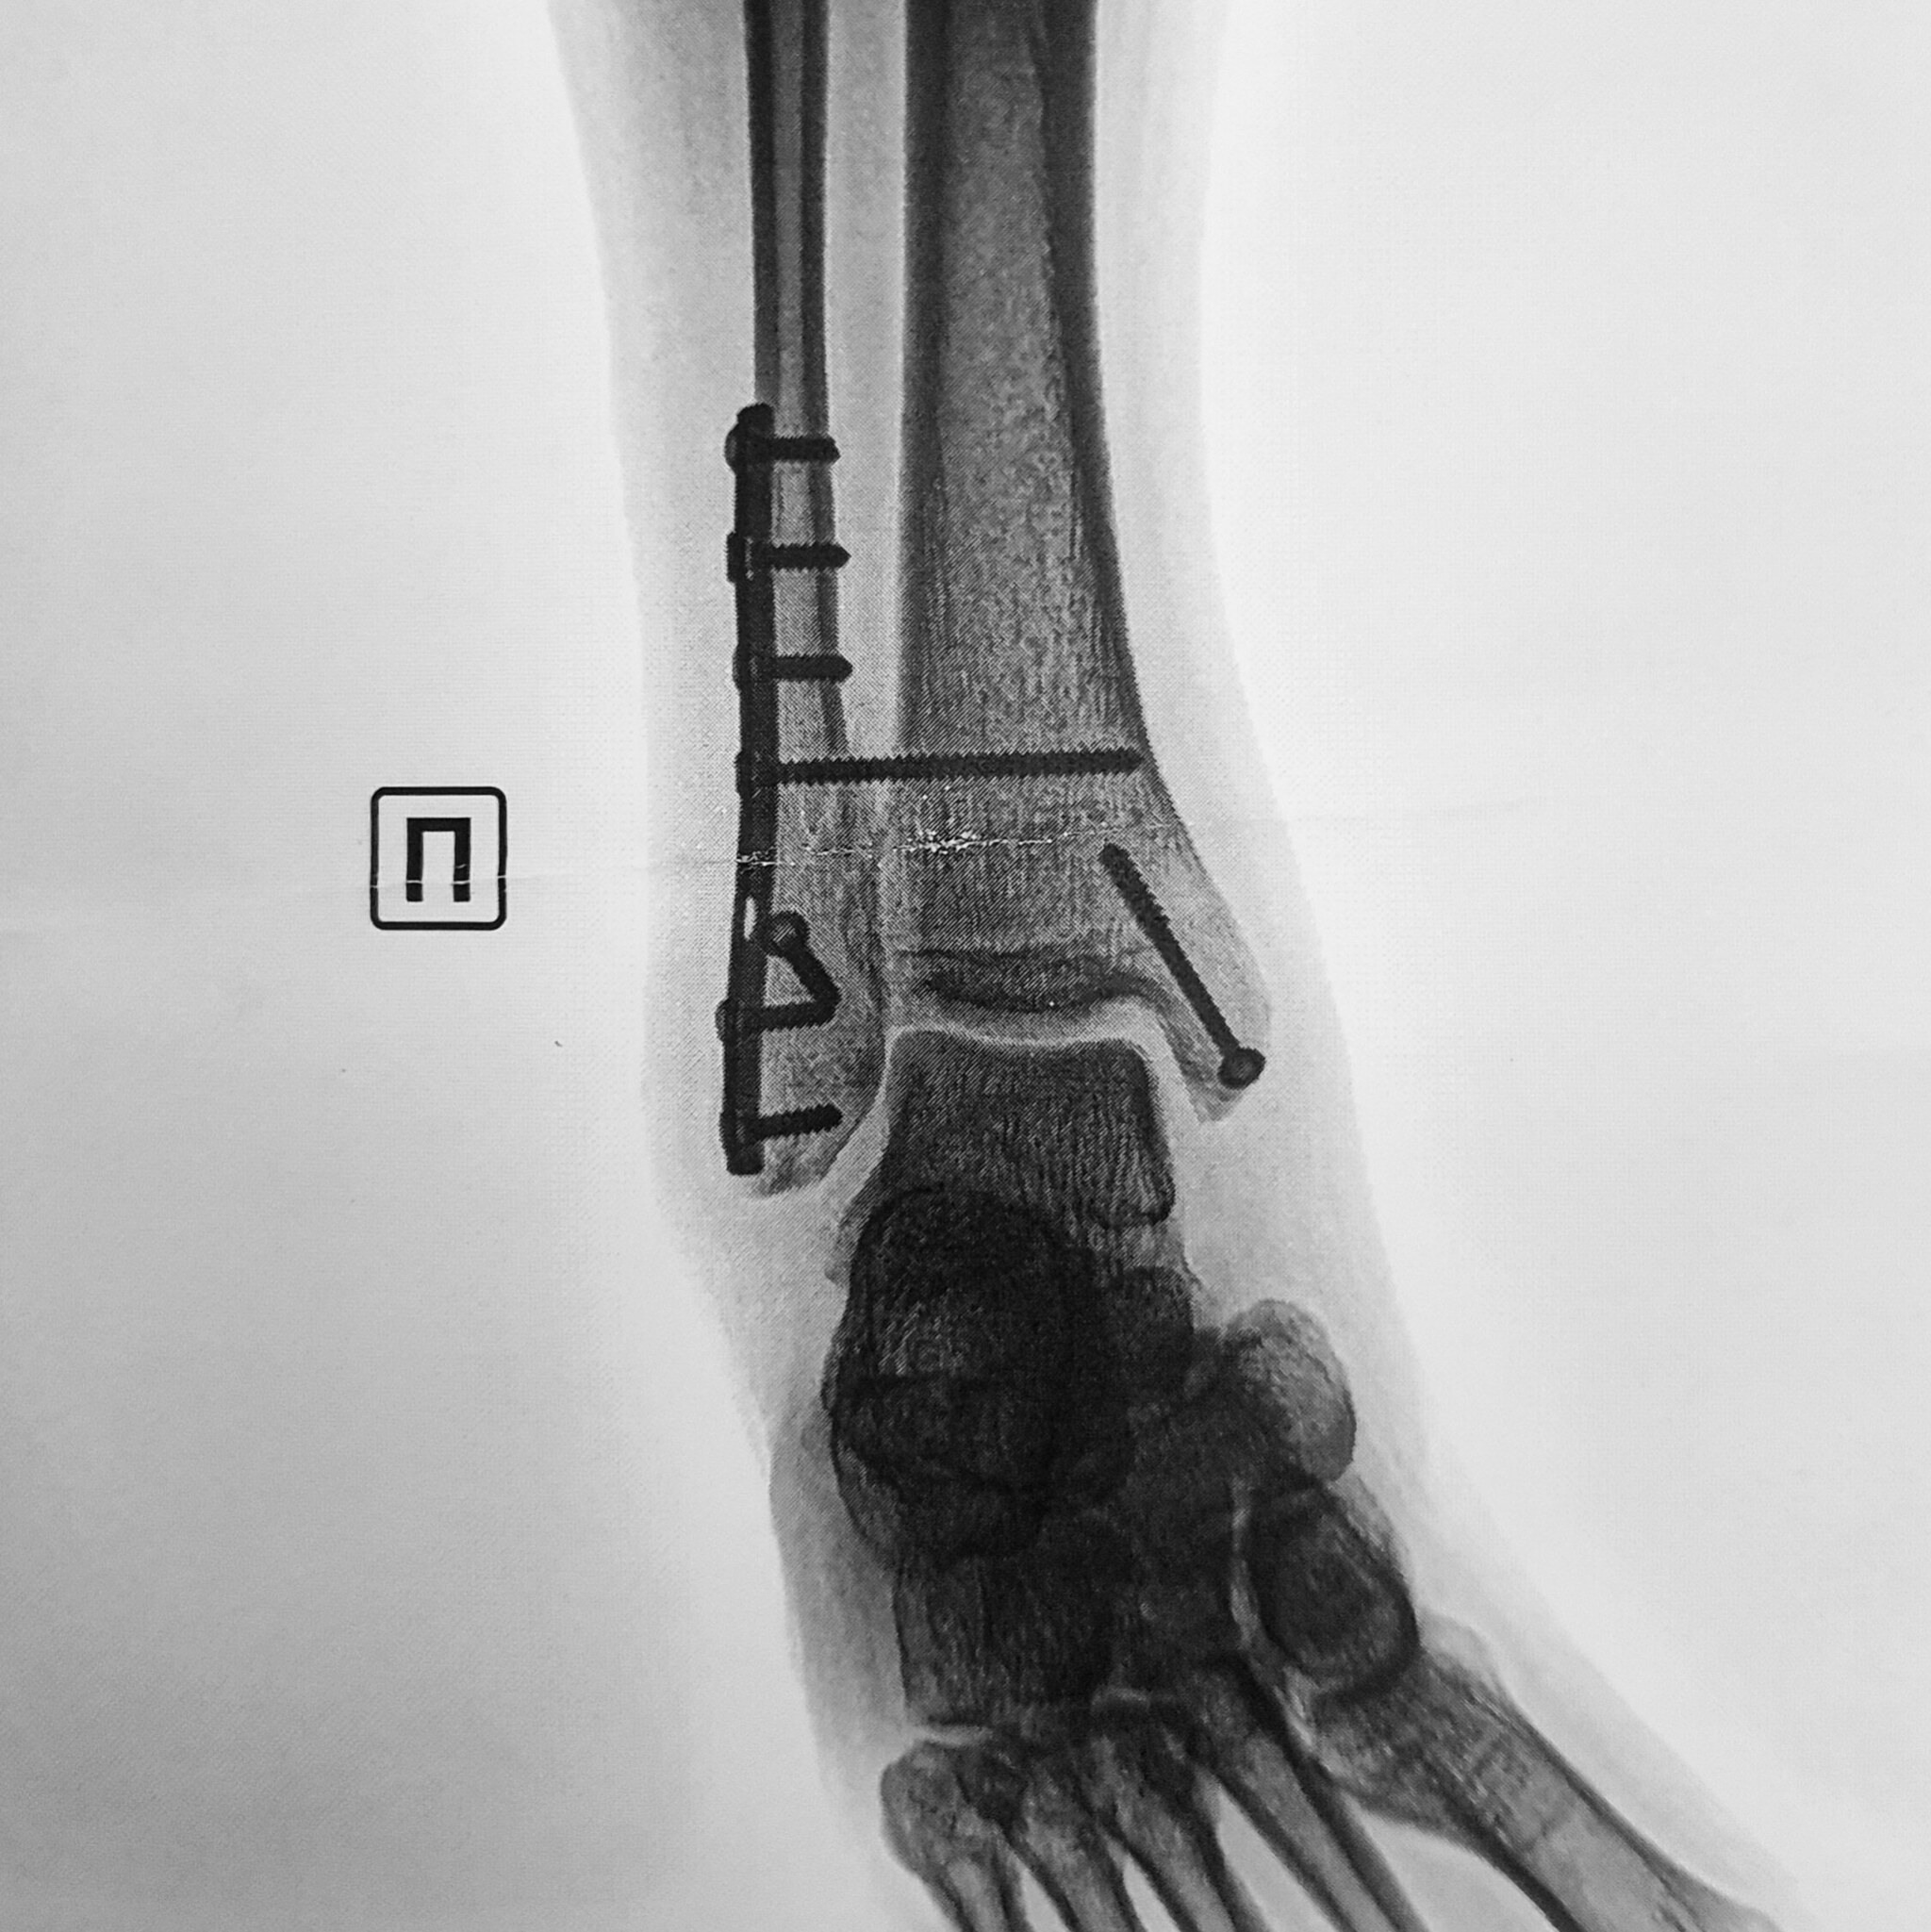

Интересно, у меня тоже левая нога, 2 пластины на МБК и ББК, ходил недели 3 на iwalk, потом на двух подмышечных костылях, потом на одном, сейчас трость, пытаюсь ходить без неё, тоже могу начать прогулку без трости, потом в конце приходится помогать.

У меня ДТП. Я за рулём, на меня на встречку вылетел лоб в лоб. Очнулся в больнице. Левую ногу и левую руку собирали. Вот на руке шрам страшный. Из последствий нога короче на 3см. Спец обувь. А так, спустя 1,5 года всё отлично)))) но металл пока во мне. Не знаю, буду вынимать или нет. И так натерпелся операций, не хочу....